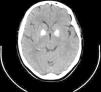

Fahr's disease

Enfermedad de Fahr